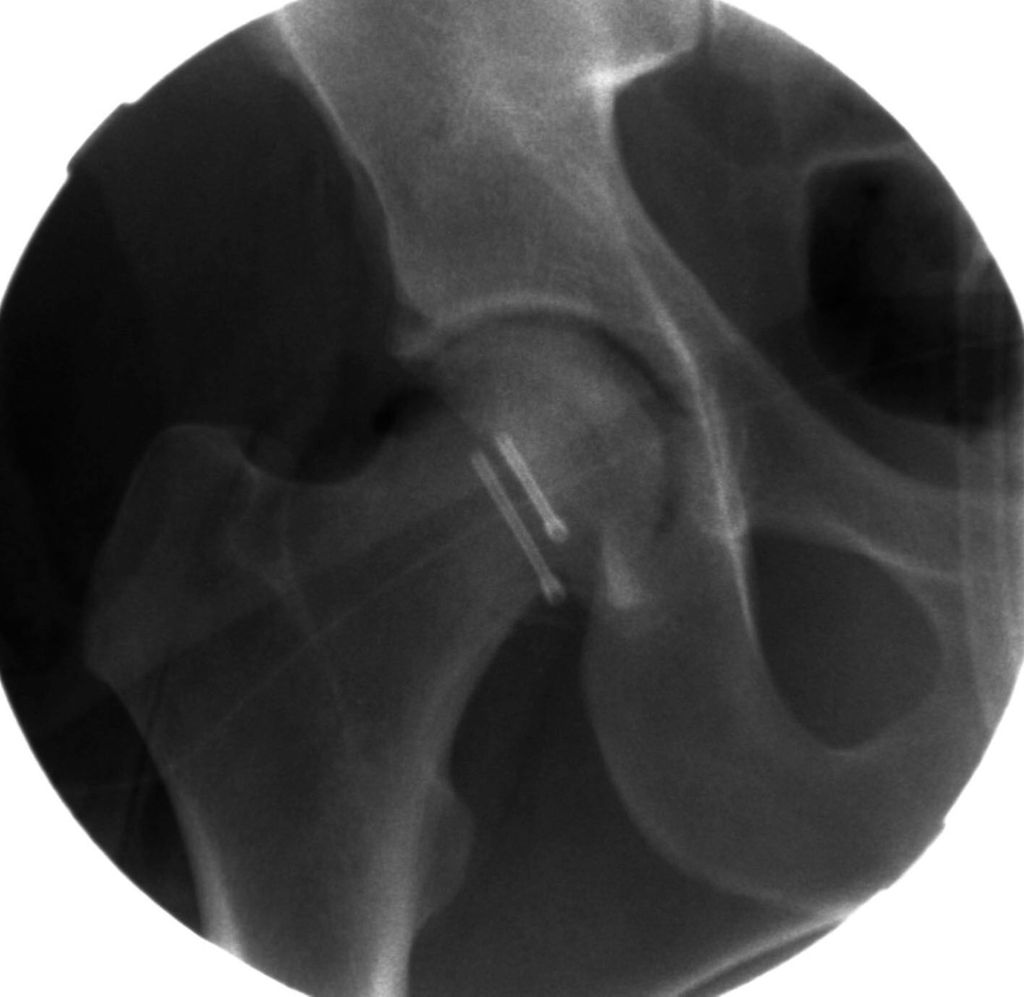

Abb. 1: Neben der klinischen Erstuntersuchung und Anamnese umfasst die Diagnostik die konventionelle native Röntgendiagnostik des verletzten Hüftgelenkes mit Standardaufnahmen im a.-p. und axialen Strahlengang. Abgebildet wird die erste Röntgenaufnahme (Hüftübersicht) nach Einlieferung in den unfallchirurgischen Schockraum nach Verkehrsunfall

Neben der klinischen Erstuntersuchung und Anamnese umfasst die Diagnostik die konventionelle native Röntgendiagnostik des verletzten Hüftgelenkes mit Standardaufnahmen im a.-p. und axialen Strahlengang (Abb. 1, 2) sowie gegebenenfalls die Anfertigung von Ala- und Obturatoraufnahmen. Obligatorisch empfehlen wir die Anfertigung eines Hüftübersichtsröntgens und gegebenenfalls, sofern möglich, auch eine Faux-Profil-Aufnahme. Zur präoperativen Planung und zur Beurteilung des Repositionsergebnisses ist der Goldstandard die Computertomografie (Abb. 3) mit Anfertigung einer 3D-Rekonstruktion. Im Rahmen der Notfalldiagnostik spielt die Magnetresonanz keine wesentliche Rolle. Im Hinblick auf die Diagnostik sekundär auftretender Komplikationen ist jedoch die Bedeutung des MRT unumstritten.